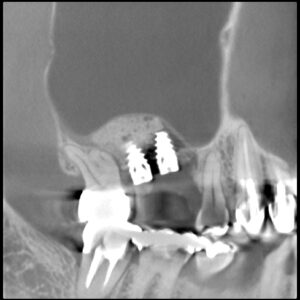

サイナスリフトとは  (2018年3月の症例 50代男性)